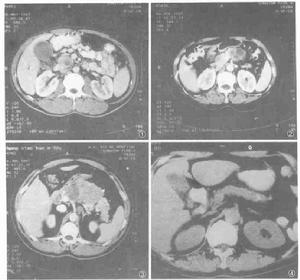

胰頭癌轉移性胰腺癌:肺、乳腺、卵巢、前列腺、肝、腎和胃腸道的癌腫均可轉移到胰腺。胰腺是轉移癌的好發部位。轉移性胰腺癌的CT表現多種多樣,大致分為3種情況,即單發不規則腫物、多發腫物和胰腺瀰漫性腫大。其中以單發腫塊最多見,而單發腫塊多位於胰頭部。轉移灶的大小依檢查時間早晚不同各異,其形態大多呈不規則狀,部分可見分葉,密度上表現為低密度及等密度,但以低密度為主。形態與密度改變沒有明顯特異性,但從局部表現很難與原發腫瘤區別,必須密切結合臨床及其他一些間接徵象加以辨別。原發灶明確是診斷的前提,所以診斷並不十分困難。

胰腺多發腫物比較容易引起轉移,如果原發灶確定,可以診斷。但是胰腺癌應與急性胰腺炎、全胰癌鑑別。急性壞死型胰腺炎有時因低密度壞死與胰實質緊貼在一起似胰腺多發性瀰漫轉移,但強化後實質邊界不清,胰周有低密度水腫帶,臨床症狀典型可以鑑別。部分全胰癌表現為胰腺多發病灶和灶性瀰漫性腫大時,二者鑑別較困難,須緊密結合臨床病史。

此外,部分慢性胰腺炎表現為胰腺局限性腫大,特別是位於胰頭部的胰腺增大與胰頭癌極為相似,以下幾點可以鑑別:

總之,胰頭癌表現形態多種多樣,診斷時須密切結合臨床,以提高診斷率,CT仍為重要檢查方式